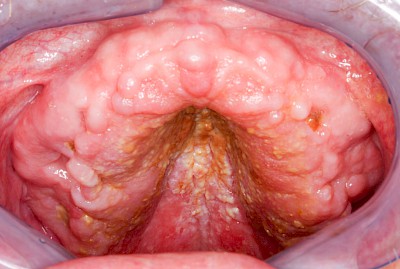

Pilzerkrankung

Pilze gehören zur physiologischen Mundflora und sind grundsätzlich nicht problematisch. Schlechte Mund- bzw. Prothesenhygiene und ggf. gleichzeitig übermäßiger Verzehr kohlenhydratreicher Nahrung kann das Pilzwachstum jedoch begünstigen Der typische Pilz im Mund ist Candida albicans, ein sprossbildender Hefepilz. Bei übermäßigem Pilzwachstum spricht man von einer Pilzerkrankung, Pilzfinfektion, Pilzbefall, Soor oder Candidose. Pilzerkrankungen können auch im Fall guter Mundhygiene auftreten bei:

Wenn die Intensivierung der Mundpflege allein den Pilzbefall nicht zu verhindern vermag, sind in manchen Fällen dann zusätzliche Maßnahmen wie Medikamente gegen Pilze (Antimykotika) nach ärztlicher Rücksprache angezeigt.

Beispiele25 Bilder